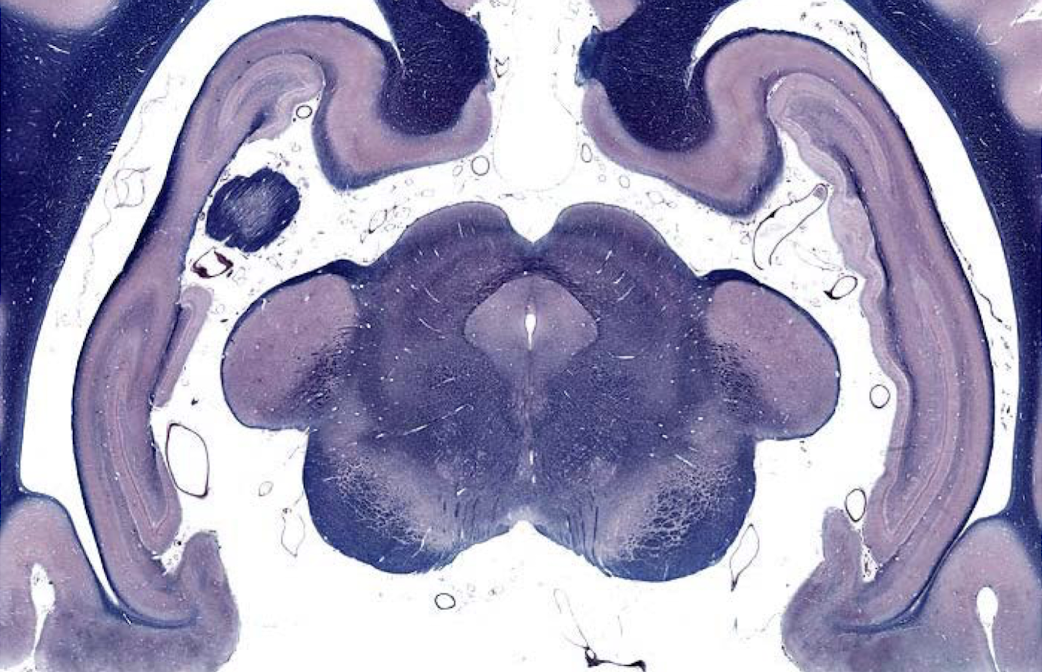

what section of the brain is shown?

caudal medulla

- open 4th ventricle

- olivary nucleus

- pyramids (indicate medulla)